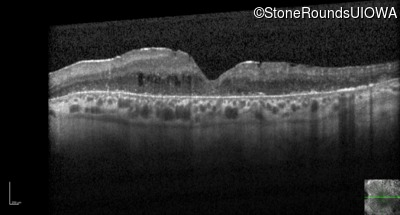

Optical Coherence Tomography - Right - 20/150

Exemplar / OCT Stack

OCT Stack